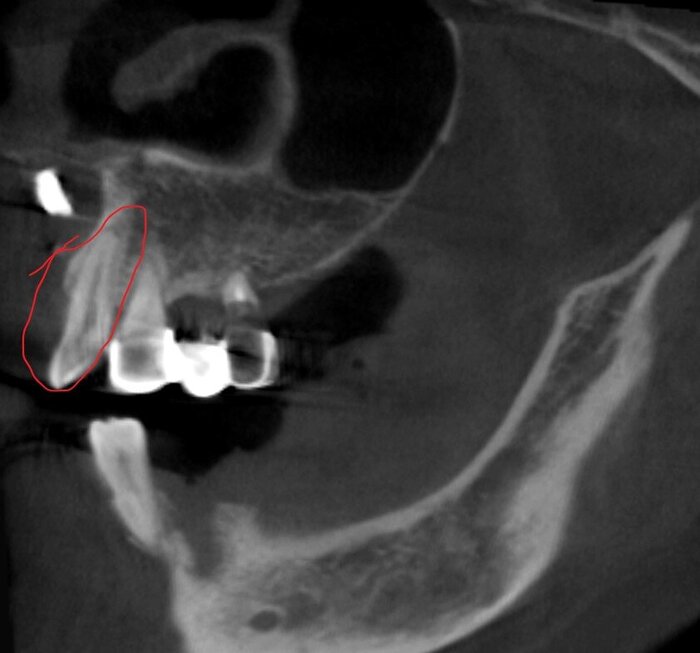

Получилось так, что сверху всего 8 зубов, по 4 с каждой стороны. Чёрная точка (которую вы точно увидите, скос эмали на зубе 1.1) - конструктивные особенности, всё это будет закрыто пломбировочным материалом. Зуб 1.1 - дополнительный имлантат, который потом планируем убрать. Он нужен лишь для усиления, ибо торк полноценный был получен только на одном из остальных 6-ти установленных.

Так же важный момент - верхний протез соприкасается с нижним только в точках полученного торка (их всего 2), остальное "на весу" и жевать не способно.

Шахты имплантатов закрыты временным материалом на 2 дня, он не очень эстетичный по цвету.

В понедельник винты будут подтянуты, а шахты закроются постоянным пломбировочным.

Поднутрения, дефекты слизистой - на то протезы и временные адаптационные, что костная ткань должна перестроиться и прийти в себя перед постоянным протезированием.

Главное - всё комфортно. Этот вариант, действительно, отвечает физиологии мышц.